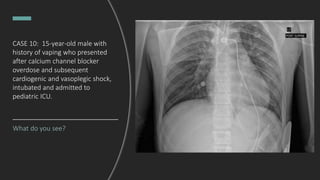

CASE 10: 15-year-old male with

history of vaping who presented

after calcium channel blocker

overdose and subsequent

cardiogenic and vasoplegic shock,

intubated and admitted to

pediatric ICU.

What do you see?

Endotracheal tube in good position.

Hazy perihilar opacities.

DDx: pulmonary edema, aspiration

pneumonia